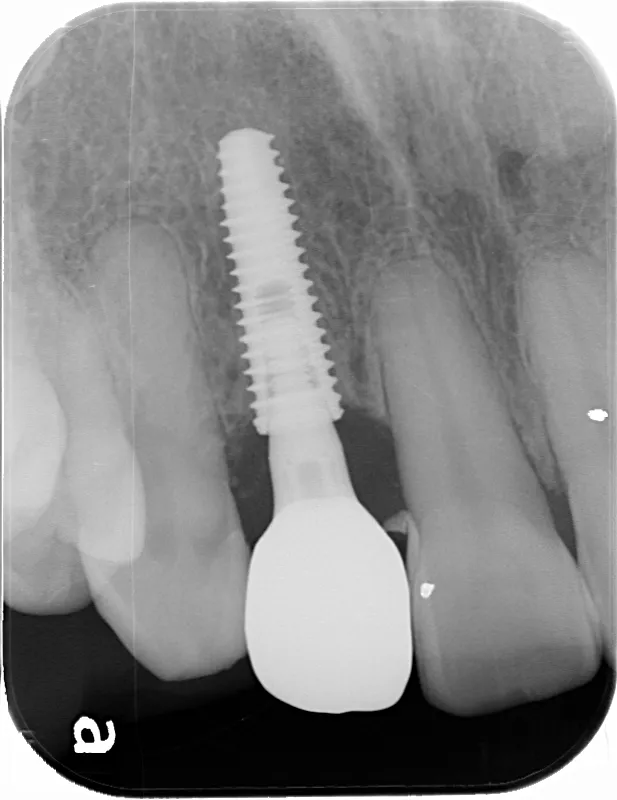

症例2/

臼歯1本

- 治療期間

- 3ヶ月

- 費用

- 51万円(税込)

治療前

治療後

レントゲン画像

治療内容

第一大臼歯1歯欠損をインプラントで回復したケースです。第一大臼歯は永久歯の中で一番最初に生える歯ですが、一番早く傷んでしまう歯でもあります。噛む力の60%を負担し噛み合わせの安定に大きく影響しますので、この歯が欠損すると噛み合わせに悪い影響を与えてしまいます。インプラントで治すことにより噛み合わせが安定するだけでなく、ブリッジのように隣在歯を削らないので天然歯の寿命を延ばすメリットもあります。